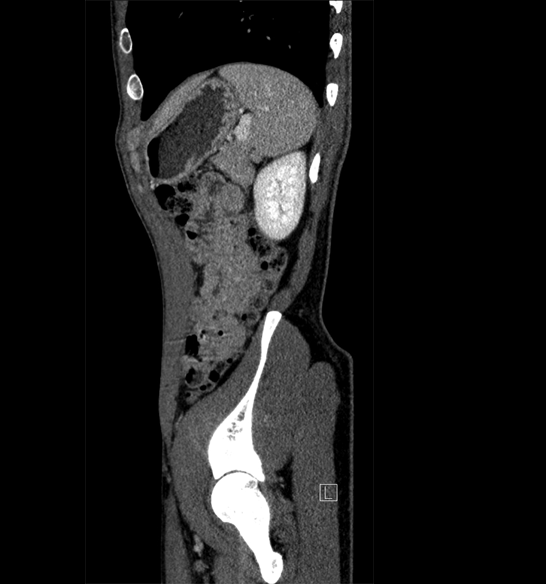

Body

Covers abdominal CT anatomy.